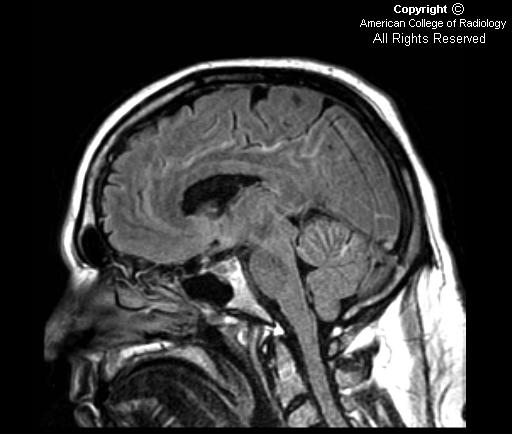

FindingsFigure 1, Figure 2, Figure 3, and Figure 4: Postgadolinium T1 weighted images demonstrate linear contrast enhancement in the subarachnoid space, most notably interdigitating between the folia of the superior cerebellum and in the sulci of the parietal and occipital lobes. The T1 weighted precontrast images are unremarkable.

On FLAIR imaging in Figure 5, there is corresponding hyperintensity in the subarachnoid space.

Contrast enhanced MR imaging is the diagnostic test of choice as an adjunct to CSF cytology when leptomeningeal metastases are suspected. Gadolinium enhanced MRI is more sensitive than a single lumbar puncture, but is less specific. The most common imaging findings include diffuse leptomeningeal contrast enhancement, multiple masses or nodules within the subarachnoid space and/or hydrocephalus. The diffuse leptomeningeal enhancement pattern has been referred to as sugar-coating or zuckerguss (German for icing or sugar-coating). Studies have shown that contrast-enhanced T1-weighted MR imaging is the most sensitive single sequence for detection of leptomeningeal metastases.